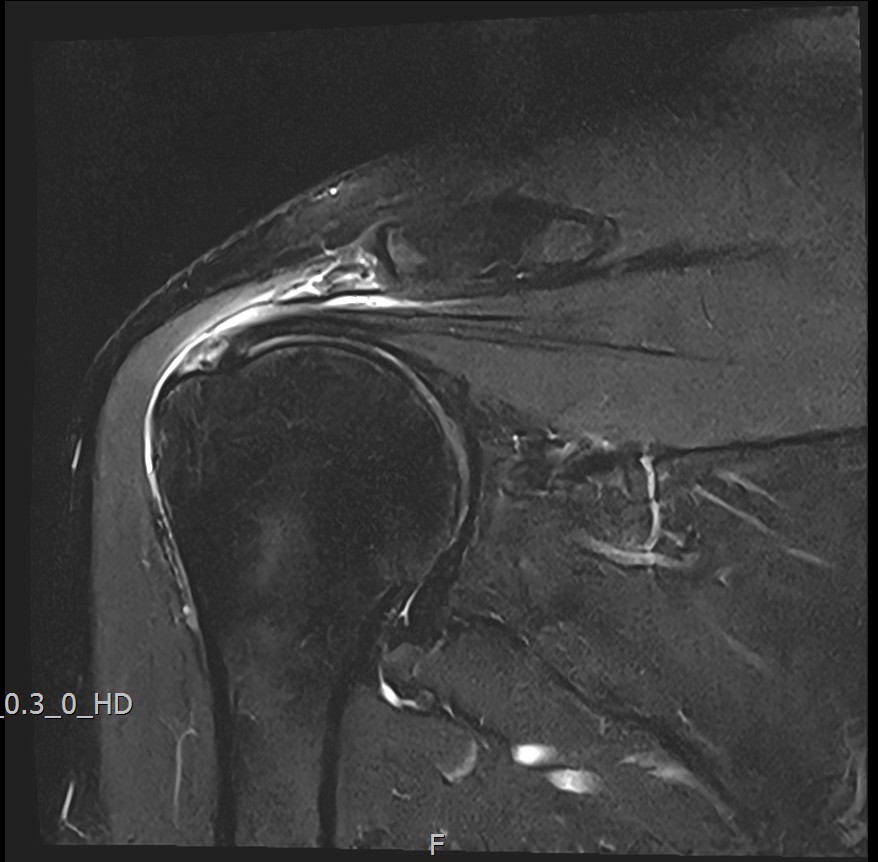

MRI를 검토해보았습니다.

회전근개 극상건의 점액낭면측(bursal-side) 부분파열. 처음보다 파열 범위가 약간 넓어져 있었고, 인대가 얇아진 소견도 보였습니다.

MRI: 극상건 점액낭면측 부분파열

인대 두께: 4.2mm (정상 5~6mm보다 얇음)

1년간 주사치료 3회, 반복 재발

6개월 후 MRI: 인대 두께 5.8mm (1.6mm 증가)